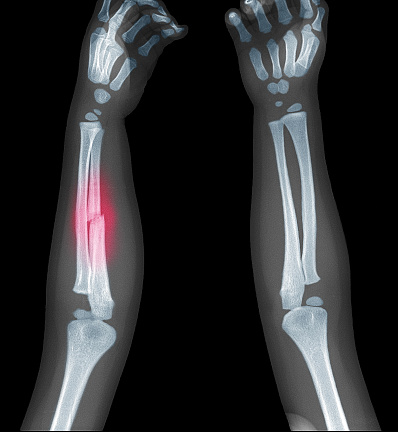

Fractures are one of the most common injuries in children, often occurring due to their active lifestyles. Whether from falls, sports, or accidents, children’s bones are more prone to fractures because they are still growing and more flexible compared to adult bones.

Children’s bones differ significantly from those of adults. The bones of children are still growing and contain cartilage, which makes them more flexible and prone to specific types of fractures, such as greenstick or buckle fractures. These fractures are typically less complicated but require specialized care to prevent them from affecting bone growth. The treatment approach for children’s fractures must be precise, ensuring that the bones heal in the proper alignment while minimizing the risk of growth disturbances.